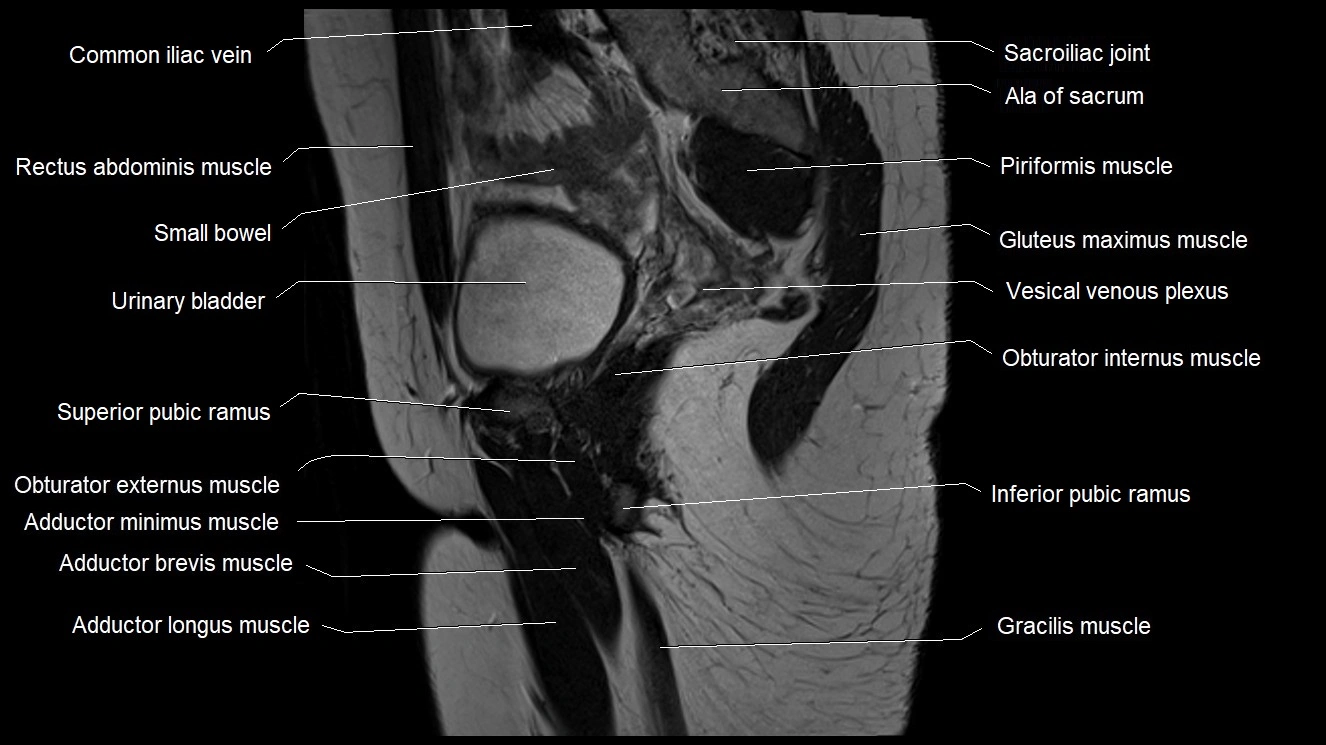

- Adductor brevis muscle

- Adductor longus muscle

- Common iliac vein

- Gluteus medius muscle

- Gracilis muscle

- Inferior pubic ramus

- Obturator externus muscle

- Obturator internus muscle

- Sacroiliac joint

- Superior pubic ramus

- Urinary bladder